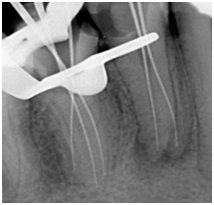

A 35‑year‑old female patient walked into our clinic with the chief complaint of severe pain in the lower jaw right posterior region since 2 days. Oral examination revealed occlusal caries in the lower right mandibular first premolar and secondary caries in second premolar. The tooth was sensitive to percussion and showed an exaggerated response on cold and electric pulp testing. Radiological findings showed coronal radiolucency involving pulp, widening of periodontal ligament (PDL) space, large pulp chamber without any constriction at cementoenamel junction, the condition was diagnosed as acute irreversible pulpitis with apical periodontitis in both the premolars (Figure 1) Cone-beam computed tomography (CBCT) was carried out for confirming numbers of roots and canals of mandibular right second premolar. The CBCT images were taken out using three‑dimensional (3D) Accuitomo scanner (J. Morita, Kyoto, Japan), with Viewer Plus software (J. Morita), which produced a smallest field of view images, to reduce the radiation dosage. A three canals were found, two buccally and one lingually (Figure 2). A non‑surgical root canal treatment was planned accordingly. The patient received local anesthesia with 2% lidocaine and 1:100,000 epinephrine and the rubber dam placement. Following the removal of old filling, careful examination of the pulpal floor revealed three separate mesiobuccal, distobuccal and lingual orifices. The access cavity outline was modified into triangular shape to establish straight‑line access for all root canals. The working length was established using Root ZX II (J. Morita, Tokyo, Japan) and confirmed radiographically (Figure 3). Instrumentation is achieved with Hero Shaper (Micro Mega) to size 30 4%, copious irrigation with 2.5% NaOCl and 17% EDTA was carried out during the instrumentation phase. All canals were dried with sterile paper points and then filling using matching gutta‑percha cones and AH‑plus sealer (Dentsply Maillefer, Ballaigues, Switzerland) until canal orifices (Figure 4) Postendodontic restoration was done followed by tooth preparation and Zirconia‑based full coverage crown cementation. Fifteen months follow‑up radiograph revealed satisfactory healing and healthy status of periapical tissues (Figure 5).

Figure 3 Working length determination.